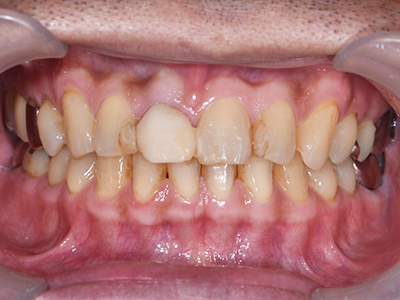

前から見ても歯が欠けてしまい、歯茎も赤く腫れてしまっているのが分かります。

下の口腔内写真は初診時と矯正治療+補綴治療後のものになります。

連結してあった前歯の被せ物(歯茎まで黒くなっている)も矯正後にきれいに治療することが出来ています。

歯並びが悪いと見た目が悪いだけではなく歯磨きがしづらく、噛み合わせが悪いことで力のかかり方が不均一になってしまい歯に亀裂が入り虫歯になりやすくもなります。